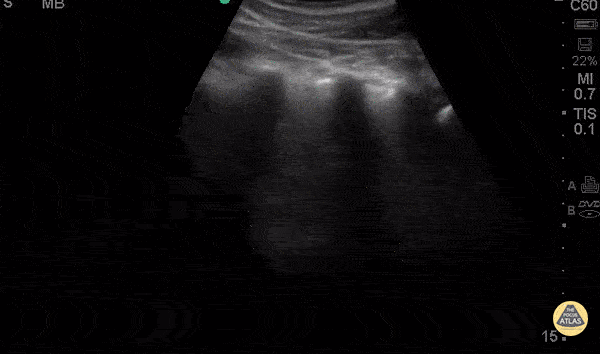

Pediatrics - Focal B-lines - Pneumonia

2 years old male with hx of endotracheal intubation secondary to RSV infection presents with 2 days of fever, cough, rhinorrhea and nasal congestion. Denied nausea, emesis, diarrhea, chest pain, syncope, confusion, change in eating patterns and voiding patterns. POCUS demonstrates a focal area of B lines c/w pneumonia (likely viral). Early PNA B lines: short path reverberation artifacts create by fluid filled alveoli. In the appropriate clinical scenario B lines and pleural consolidation suggest PNA. Dr. Carolina Camacho Ruiz - Kings County Emergency Medicine